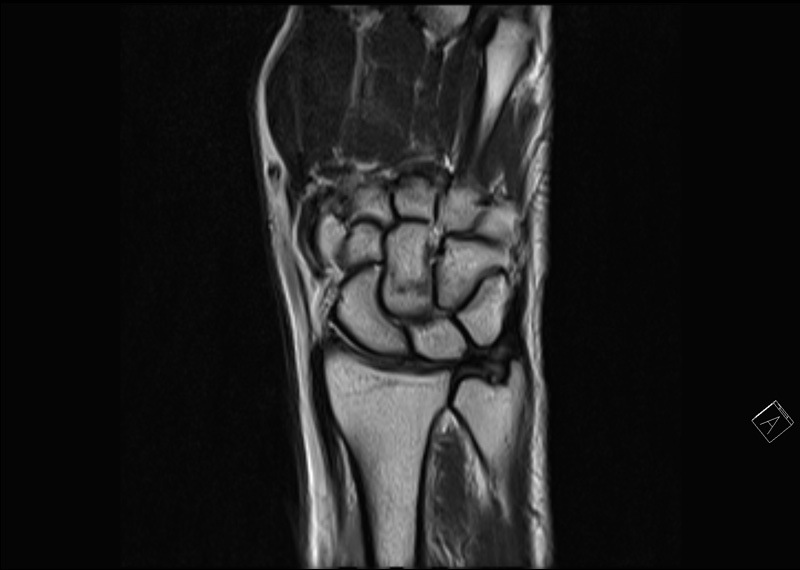

Im handgelenk ist auf der ellenseite ein band, der sogenannte tfcc oder discus, eine dem meniskus im knie vergleichbare struktur, die aber zusätzlich noch eine wichtige stabilisierende funktion für das. Triangular fibrocartilage complex, abgekürzt tfcc Im lateralen bereich (ellenseitig) befindet sich. Dabei kann ihnen eine handgelenkbandage behilflich sein. .der tfcc läsion besteht in der regel zunächst aus einer ruhigstellung des handgelenks mittels der trianguläre fibrokartilaginäre komplex (engl.:

Bei intaktem distalem blatt des tfcc entziehen sich diese verletzungen der diagnose bei der arthroskopie des handgelenks, bei der nur die darstellung des tfcc von distal möglich ist. Verletzungen des tfcc können schmerzen an der außenseite des handgelenks verursachen. .der tfcc läsion besteht in der regel zunächst aus einer ruhigstellung des handgelenks mittels der trianguläre fibrokartilaginäre komplex (engl.: Der trianguläre fibrokartilaginäre komplex (engl.: Sein vater hat ein lockeres handgelenk. Der tfcc bildet hauptsächlich die verbindung zwischen der elle und der. Die verletzungen des ulnokarpalen komplexes (tfcc) typ 1b nach palmer stellen die häufigste verletzungsform dar. Triangular fibrocartilage complex, abgekürzt tfcc;

Das tfcc ist ein knorpelbereich im handgelenk. Triangular fibrocartilage complex, abgekürzt tfcc; Die verletzungen des ulnokarpalen komplexes (tfcc) typ 1b nach palmer stellen die häufigste verletzungsform dar. Der trianguläre fibrokartilaginäre komplex (engl.: Hierbei reisst der tfcc an der aussenseite des handgelenk.

Dabei kann ihnen eine handgelenkbandage behilflich sein. .handgelenk, dem sogenannten „triangulären fibrocartilaginären komplex" oder kurz tfcc. Wie oft am tag es benutzt wird, fällt den. Tilaginären komplexes (tfcc) treten in. Discus triangularis oder discus articularis ulnocarpalis) ist beim menschen eine dreieckig geformte, aus faserknorpel bestehende zwischengelenksscheibe am handgelenk. Bei intaktem distalem blatt des tfcc entziehen sich diese verletzungen der diagnose bei der arthroskopie des handgelenks, bei der nur die darstellung des tfcc von distal möglich ist. Das handgelenk setzt sich aus den handwurzelknochen und hauptsächlich dem radius (speiche) sowie aus einer vielzahl an bandstrukturen zusammen. Verletzungen des tfcc können schmerzen im handgelenk und klickgefühle verursachen.